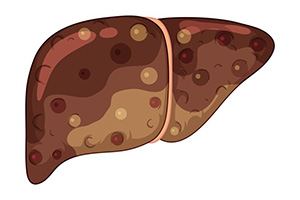

de la síntesis hepática de triglicéridos, ya que el EPA y el DHA son malos sustratos para las enzimas responsables de esta síntesis.

de la B-oxidación de ácidos grasos en los peroxisomas del hígado, lo que reduce la cantidad de ácidos grasos libres disponibles para la síntesis de triglicéridos.